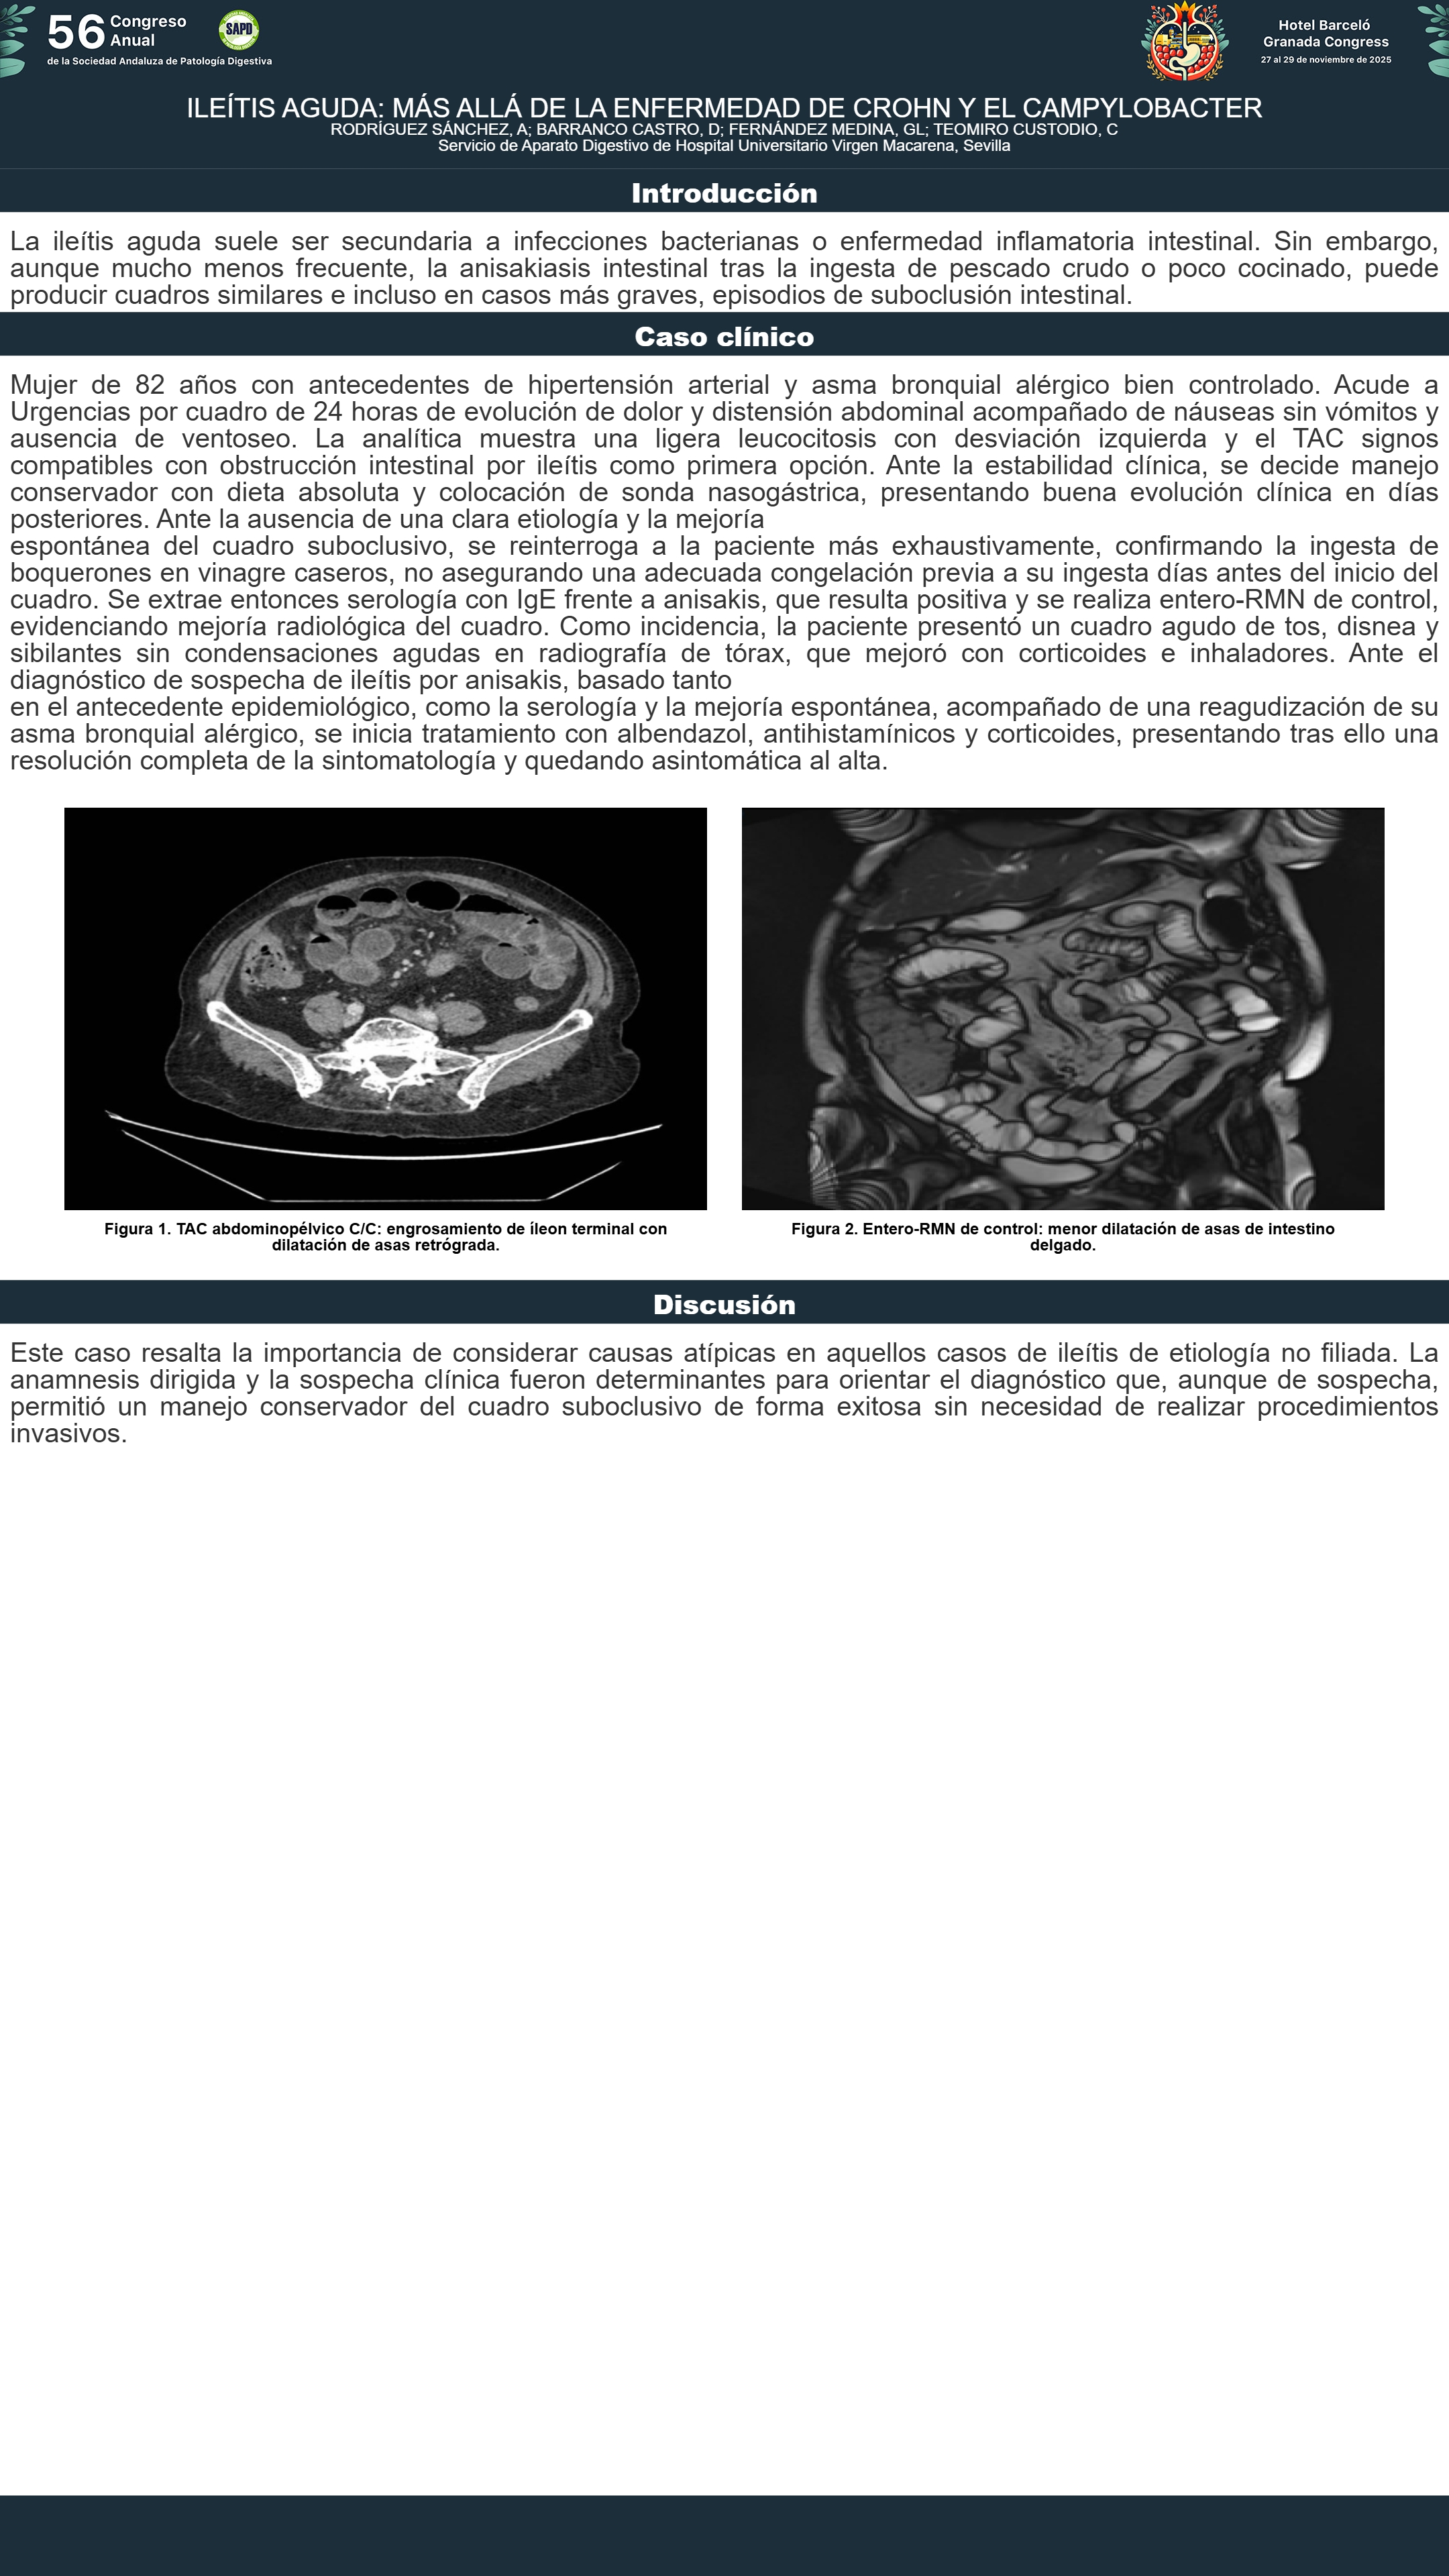

[CP-009] TUMOR NEUROENDOCRINO ILEAL: UNA CAUSA INFRECUENTE DE ANEMIA FERROPÉNICA